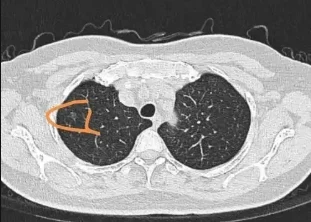

肺部微结节的成因包括感染、炎症反应、结核、良性肿瘤甚至早期恶性肿瘤。CT扫描是目前最佳的影像学检查方法,可以高分辨率地呈现微小结节的具体情况。结节的大小、边界特征及内部密度等特点均可帮助医生判断。

根据《Journal of Clinical Oncology》(JCO)的研究,微结节的大小大于8毫米的患者需要进行定期的随访和观察(每3-6个月一次)。此外,CT影像中若发现结节的边缘呈不规则或毛刺状,其癌变可能性更高。这些特点在临床上会影响医生对结节性质的判断和处理方式。